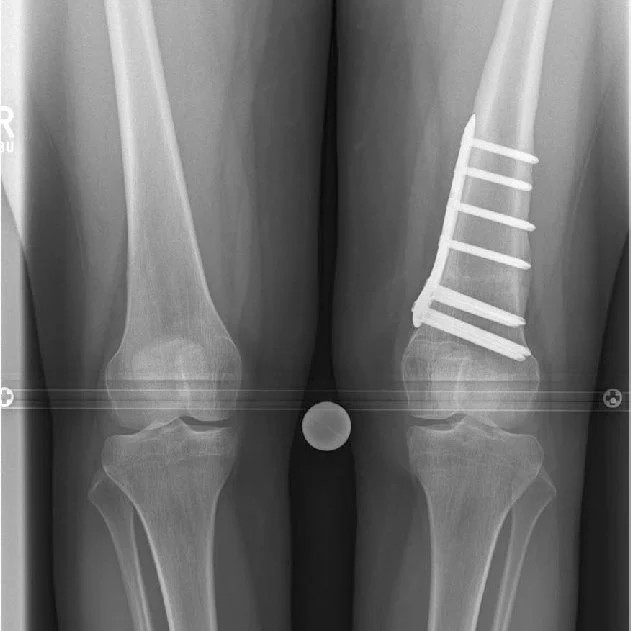

Knock Knees, also known as genu varum, is a condition where the legs appear bowed outwards when standing. This condition can cause discomfort, pain, and even difficulty walking. In severe cases, surgery may be required to correct the alignment of the legs. In this article, we will discuss the causes, symptoms, and treatment options for Knock Knees, including the various surgical procedures available.

A doctor can diagnose knock knees by performing a physical examination and assessing the alignment of the legs. Imaging tests such as X-rays or MRI scans may also be used to confirm the diagnosis.